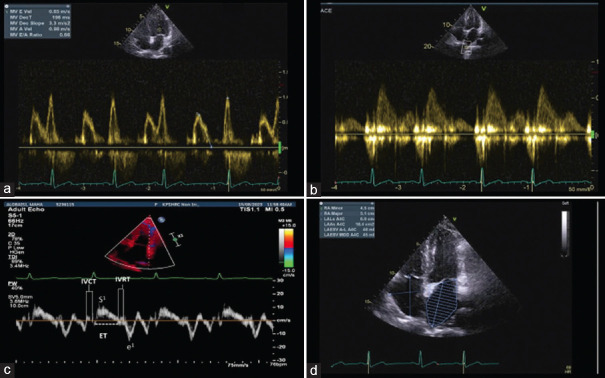

Abstract Image